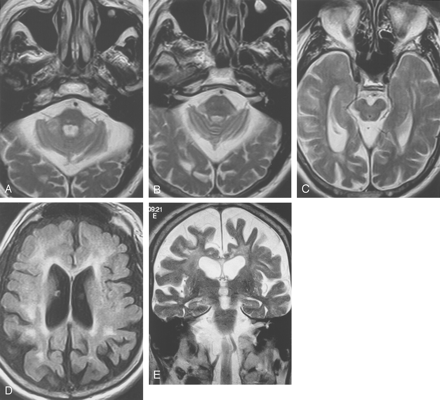

Images from the case of a 69-year-old man with fragile X premutation.

A and B, Axial view T2-weighted images show increased signal intensity in the MCPs, which are slightly thinned in the oblique transverse dimension. Prominence in size of the subarachnoid spaces can be seen. The pons shows a nonspecific right paramedian punctate area of increased signal intensity.

C, Axial view T2-weighted image. Mesencephalon and middle cerebral peduncles are mildly decreased in size, with prominence of the ambient cisterns.

D, Axial view inversion recovery image shows volume loss with increased signal intensity in frontal and parietal white matter and in the genu of the thinned corpus callosum.

E, Coronal view T2-weighted image shows volume loss and increased T2 signal intensity in the frontal white matter and in the thinned corpus callosum.